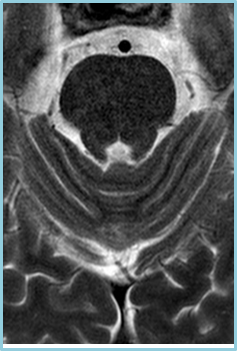

PIQE for MR

极速高分辨率成像

在磁共振领域,深度学习技术对图像进行降噪、上采样、减轻振铃伪影的处理,带来了清晰且细节丰富的图像。

过去,高分辨率图像的获取往往伴随着漫长的扫描时间,这影响了图像获取的效率,对于危重疾病的快速诊断是一大挑战。然而,PIQE技术的出现彻底颠覆了这一局面。此次发布的全新3T磁共振Galan Supreme,搭载全新的自研磁体和梯度线圈,并深度融合PIQE技术,可以实现在不增加扫描时间的前提下,轻松获取到高分辨率的图像,为临床带来了兼具高效与高质量的影像体验。